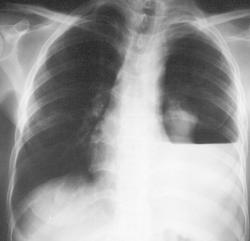

Женщина Т. 62 года. 18 дней назад была успешно оперирована по поводу рака левой молочной железы, выполнена резекция по Пити. Выписана 12 дней назад домой без ремарок. Сейчас поступила с выраженной одышкой.

Левосторонний гидропневмоторакс, м.б. даже пиопнемоторакс. Смещение средостения вправо м.б. обусловлено либо клапанным механизмом, либо активным газообразованием. Российское здравоохранение частично реабилитировано.

Уважаемый Доктор Марио! Конечно, без сомнения левосторонний гидропневмоторакс. Горизонтальный уровень жидкости. Значит имеется сообщение плевральной полости с внешним атмосферным давлением. Два вывода:

Уважаемый Доктор Марио! Постараюсь изложить свою логическую цепочку. У пациентки имеется левосторонний гидропневмоторакс с наличием горизонтального уровня жидкости. Следовательно имеется сообщение плевральной полости с внешней средой через бронх или через отверстие в грудной стенке. В ближайшем периоде было большое оперативное вмешательство именно на левой половине грудной клетки. И в первую очередь думается о травме передней стенки грудной клетки во время операции. У меня два вопроса. 1. Проводилось ли рентгенологическое исследование легких до оперативного вмешательства, каковы его результаты? 2. Проводилось ли рентгенологическое исследование легких после оперативного вмешательства, до выписки пациентки из стационара? По поводу хирургов я думаю, что шаловливые руки встречаются и у отечественных (сообщение в наших СМИ, как мохно забыть в животе зеркало 20 см в длину?) хирургов, так и зарубежных.

Третье ребро слева, по-моему, Люшка. Для оценки инфильтрации снимочки жестковаты, мне кажется, ничего определенного не скажешь. Я не вижу. Еще не будем забывать, что справа молочная железа есть, а слева нет, уже прозрачность половин грудной клетки разная!

А мне кажется, что с третьим ребром все нормально, это просто какая то дугообразная линия идет параллельно внутреннему краю ребер, возможно, обусловленная тенью мягких тканей или еще чем-то.

Уважаемый Доктор Марио! Если не ставить под сомнение заключение рентгенологов по поводу состояния легких до операции, то, прошу прощения, даю 95%(100% только БОГ) за ятрогению во время операции. Клапанный пневмоторакс. УЗИ плевральных полостей Вы уже наверное выполнили. Пункцию и дренирование плевральной полости коллеги то же уже выполнили. Вопрос- каков результат?

Конечно сдренировали, получили транссудат. Трубку поставили, лёгкое расправилось более менее.... От КТ пациентка отказалась... Мне самому очень интересно знать как так могло получится... И почему так поздно аукнулось. Я предполагаю так-во времы аоперации, когда удаляли часть грудных мышц, повредили груднуую стенку. Так как в пост-оп. регионе оставили дренажи на 4-5 дней, появилось сообщение с наружной средой, когда на 5ый день убрали дренажи-сформировалась как бы фистула.... Пациентка выписалась, дома что то усугубило её состояние и вот результат... Или другой вариант, был метастаз в бронхе-некроз-прорвалось в плевральную полость. Но это уже фантазии....

Спасибо, Доктор Марио, что удовлетворили мое любопытство! Практически, что предполагал-подтвердили. Прошу снова прощения, но поставлю под сомнение слово "транссудат". На таком сроке и этиологии минимум должен быть экссудат. И кровь была или нет?

Макро-нет. Прозрачная жидкость, немного с жетоватым оттенком. На микроскопии конечно нашли пару эритроцитов, но лаборатория дала заключение транссудат... Мне этот случай на даёт спать спокойно, жаль что пациентка отказалась от КТ, для меня многое бы прояснилось.